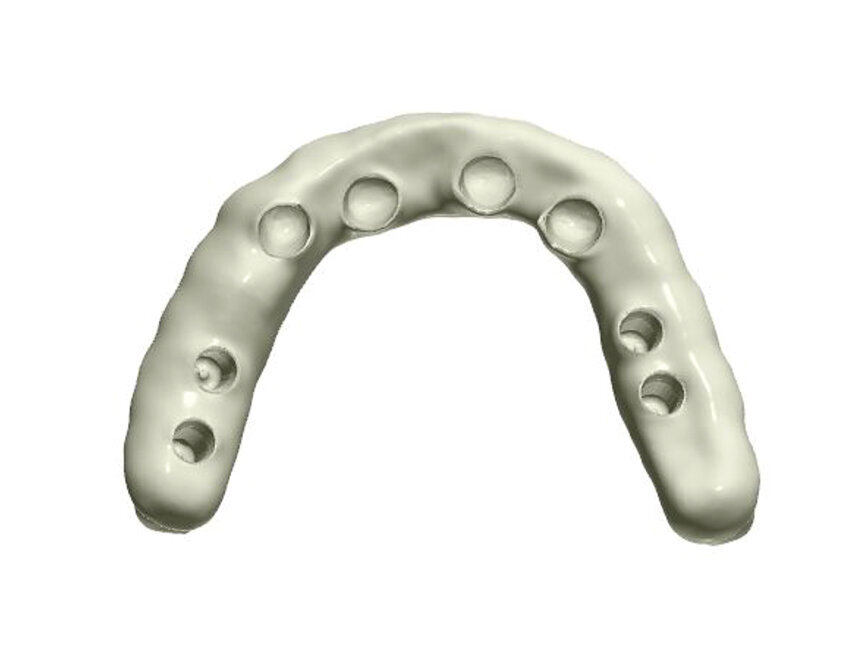

Fig. 1: A virtual image of a scanned model with abutments and telescopic crowns.

In order to prepare the bridge, a model was scanned and transferred onto a computer using software to design the bar (Fig. 1). The bar was designed by using special software in such a way that the whole design was transparent in the first phase so that the location of abutments and the position of the telescopic abutments at the frontal section could be visible (Fig. 2).